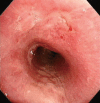

Respiratory involvement in Crohn disease (CD) is rare condition with only about a dozen reported cases. We report the first case of CD with tracheal involvement in Korea. An 18-year-old woman with CD was hospitalized because of coughing, dyspnea, and fever sustained for 3 weeks. Because she had stridor in her neck, we performed computed tomography of the neck, which showed circumferential wall thickening of the larynx and hypopharynx. Bronchoscopy revealed mucosal irregularity, ulceration, and exudates debris in the proximal trachea, and bronchial biopsy revealed chronic inflammation with granulation tissue. Based on these findings, we suspected CD with tracheal involvement and began administering intravenous methylprednisolone at 1 mg/kg per day, after which her symptoms and bronchoscopic findings improved.